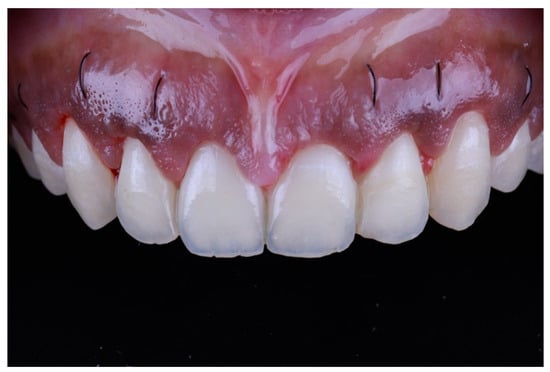

After surgery, the patient was instructed to take 600 mg ibuprofen 3 times/day for the first 7 days and to rinse with 0.12% chlorhexidine gluconate twice daily. On the 10th post-operative day, the patient presented for suture removal. Healing was uneventful (Figure 10). The patient then presented for recall at 6 weeks, and showed satisfactory outcomes at the 6 month follow-up (Figure 11 and Figure 12).

Figure 10.

At 10-day follow up.